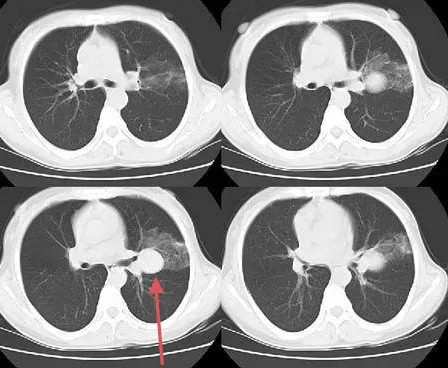

肺癌肿瘤致千疮百孔 精准靶向成功修补

图片尺寸576x492